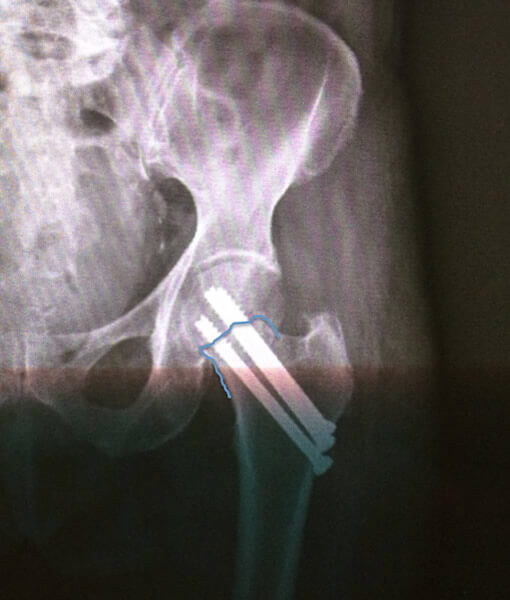

1 Fratura do Colo do Fêmur 2 Fratura do Colo do Fêmur

Fig. 1 e 2 - Fraturas do Colo do Fêmur